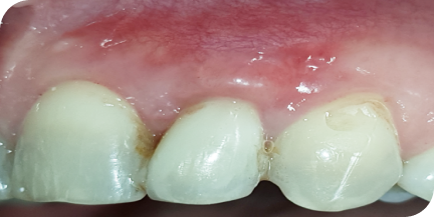

Кровоточивость дёсен и боль в них

Это признаки гингивита

Сильное воспаление дёсен с гноем или без

Это признаки пародонтита